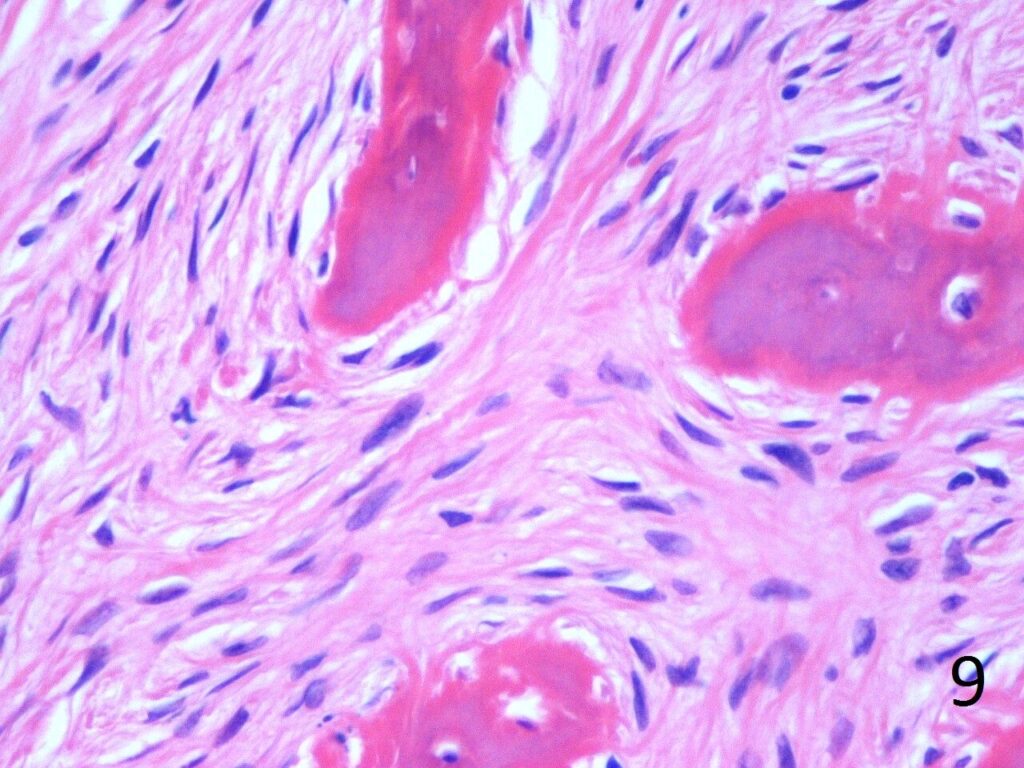

• Combination of bland hypocellular fibrous tissue with small fragments of woven bone without visible rimming by osteoblasts(Fig. 7-8) .

• Trabeculae are not lined with oteoblasts.

• No cytologic atypia is seen

Fig. 9. High power photograph of pathology of fibrous dysplasia shows woven bone being produced by the fibrous tissue. There are no osteoblasts lining the bone.